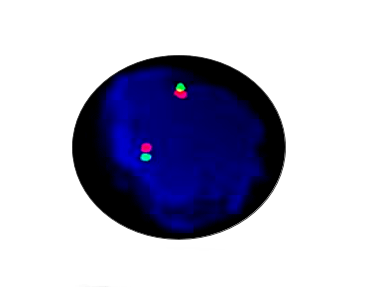

E2A Breakapart

Probe Description: E2A

Cat.No.: CF1253